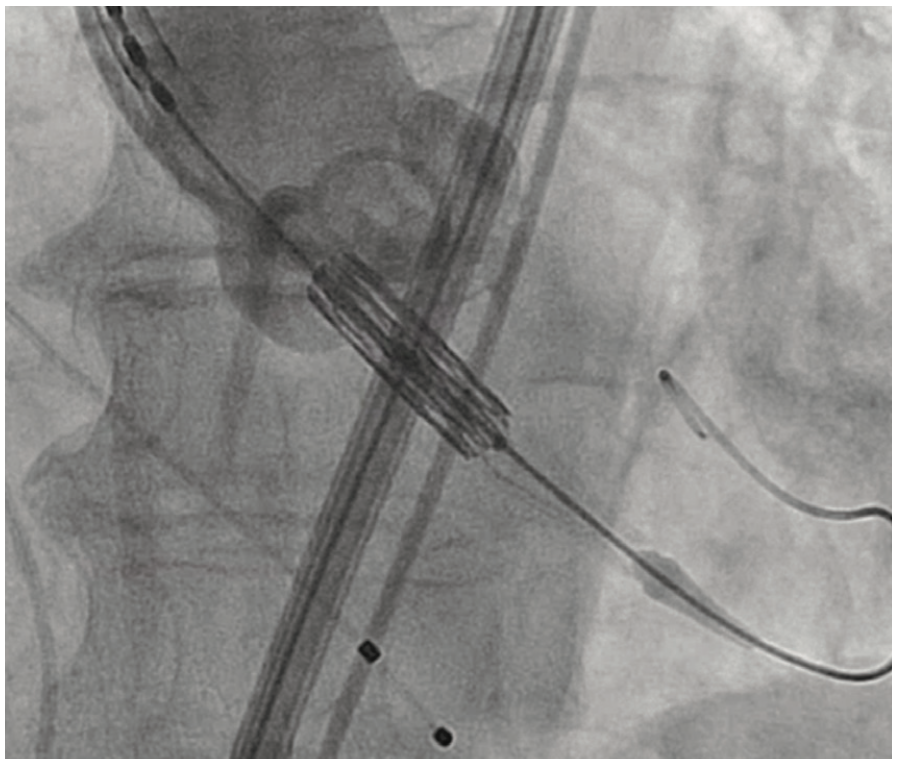

An 81-year-old female with symptomatic severe aortic stenosis, logistic EuroSCORE I (European System for Cardiac Operative Risk Evaluation) of 14.46%, EuroSCORE II of 3.44%, and Society of Thoracic Surgeons (STS) estimated surgical mortality of 3.371%, underwent TAVR. Transthoracic echocardiogram (TTE) showed a heavily calcified aortic valve with a mean gradient of 68 mmHg, aortic valve maximum velocity (Vmax) of 4.2 m/sec, calculated aortic valve area of 0.8 cm2, and normal left ventricular systolic function. Computed tomography angiography (CTA) demonstrated heavily calcified aortic root, leaflets, and annulus. Transfemoral implantation of a 23 mm Sapien 3 (Edwards Lifesciences) valve was performed (Figures 1-2). Using a 20 mm balloon for pre-dilation, the valve was implanted successfully in a 50-50 position (Figure 3). The immediate post-deployment aortogram showed leakage of dye outside the left sinus with no evidence of cardiac tamponade. Despite that fact, the patient developed immediate hemodynamic collapse. QRS widening and ST-elevation were visible on the monitor. Narrowing of the left main coronary artery (LMCA) with reduced TIMI flow (0-1) was evident in angiographic images (Figures 4-5). The patient had a cardiac arrest, cardiopulmonary resuscitation was initiated, and she went into cardiogenic shock. The patient stabilized with the placement of venoarterial extracorporeal membrane oxygenation (VA-ECMO) and the insertion of the Impella device (Abiomed) (Figure 6). An emergent percutaneous intervention was performed within minutes from collapse by the deployment of two drug-eluting stents from the LMCA into the left anterior descending (LAD) coronary artery (Figure 7) using the Culotte technique with final kissing-balloon dilatation. After the restoration of coronary flow, the patient was admitted to the cardiothoracic intensive care unit. She remained stable. The ECMO and Impella implant was removed after 7 days. Postprocedure on day 14, the patient was discharged to a rehabilitation facility. Echocardiography showed a well-functioning valve with acceptable residual gradient and mild to moderate paravalvular leak.